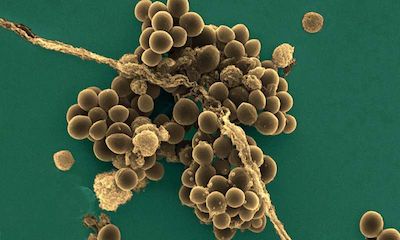

金黄色葡萄球菌的细菌

金黄色葡萄球菌的细菌

1280x991 - 372KB - JPEG

金黄色葡萄球菌

金黄色葡萄球菌

1023x602 - 200KB - JPEG